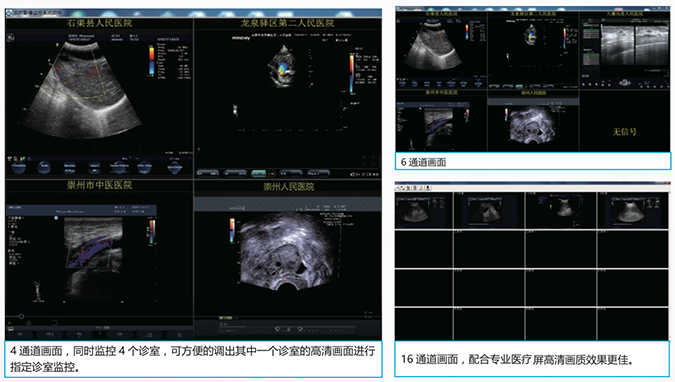

区域实时监控系统

上级医生监控